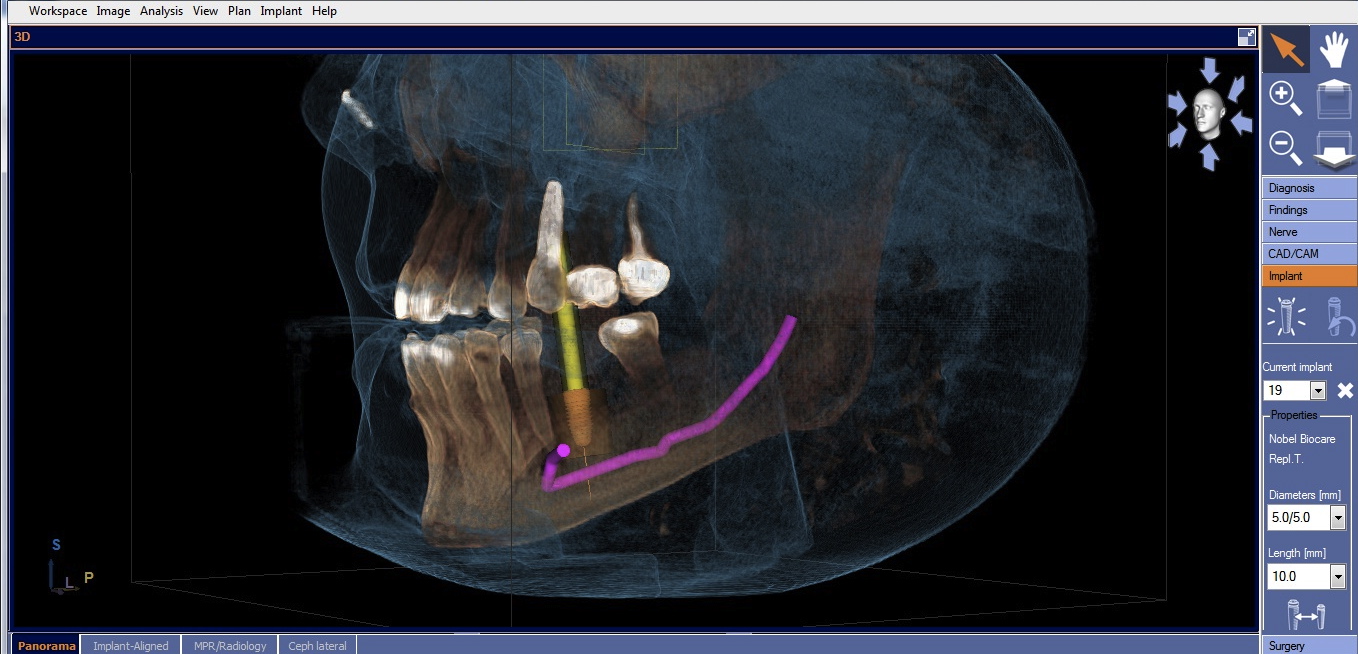

Two factors affect implant depth: distance to the proximal contact and surrounding the implant with 1 mm of bone. The implant platform should be 5 mm or less from the proximal contact for proper papilla formation.21,22 Accounting for prosthetic components, the distance to the occlusal surface should be approximately 7 mm (5 mm abutment + 2 mm ceramic). If placing the restorative platform at the osseous crest does not provide this space, it is necessary to remove bone so the implant can be submerged to proper depth. However, if placing the platform 7 mm from the restorative surface does not result in surrounding the implant with 1 mm of bone, a decision must be made. The deficiency will usually be on the facial. The practitioner must either submerge the implant until there is sufficient bone surrounding it, or if this places the implant too deeply, augment the ridge prior to implant placement. Current guided regeneration techniques can predictably gain up to 5.5 mm horizontally23 and 10 mm to 12 mm vertically.24 Once the implant platform is set, the final apical length of the implant can be adjusted and the digital plan is complete (Figure 3).

CBCT with final implant plan. Note the digital restoration, TiBase abutment, and highlighted IANB.

Figure 3